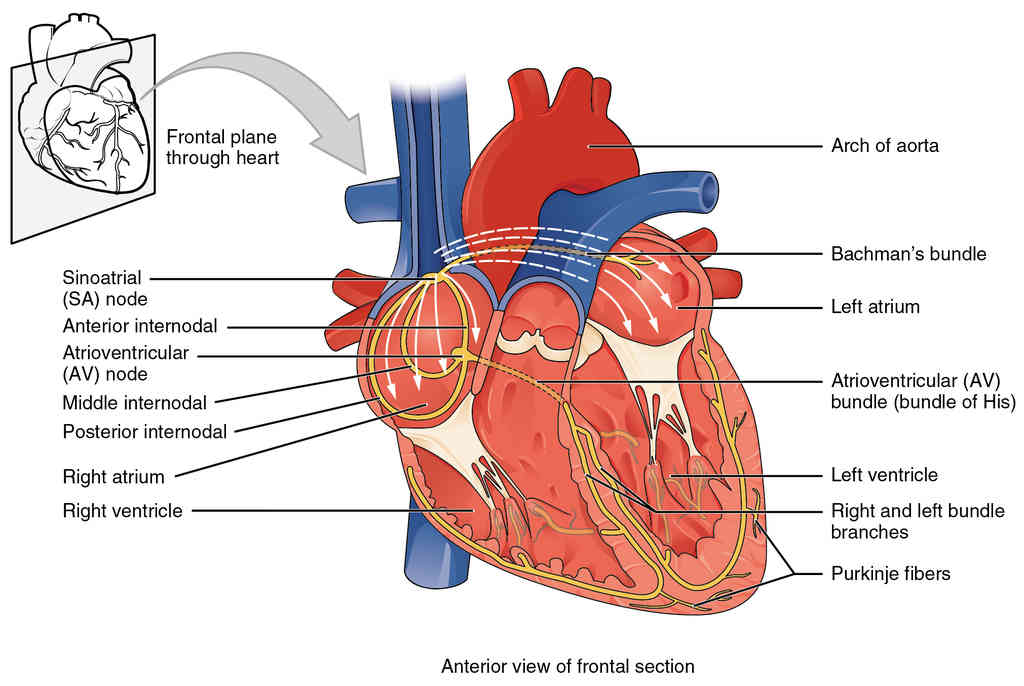

This page is under construction. For now, it is just a resource of the images found in the OpenStax Anatomy and Physiology Handbook. It wil slowly change into a revision tool. Each slide has a number. Use this to refer to the slide. When completed, it will have an unlabelled section, with labelled slides in parallel. On the unlabelled slides, write your answer and use the labelled slide to assess yourself. Keep track by also noting the number on each slide. Improvement at each attempt is important, more so than full marks on a first attempt.